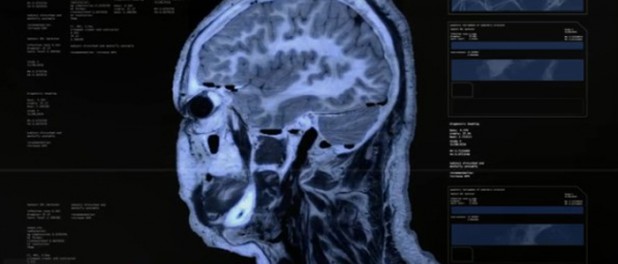

Y llega el momento de la polémica: después de algunos hits que les pusieron en la órbita de la escena dub-step, Darkstar adelantan su debut en largo (que se llamará «North» y que será publicado, como no podía ser de otra forma, por Hyperdub) con un single que poco o nada tiene que ver con lo que les conocemos. De hecho, incluso se animan a meter voces en lo que bien podría ser post-dub tamizado por la influencia de The xx. Sea como sea, preparaos a flipar: la canción es una verisón del «You Remind Me of Gold» de The Human League que se les ocurrió hacer después de escuchar la original a 33rpm. ¿Freak? No. Lo próximo. Y lo jodido es que es adictivamente nocturna… El video, por lo demás, muy hi-tech (y que aprendan algunos que la tecnología aplicada al formato clip musical no tien por qué ser aburrida.. ejem.. Radiohead).